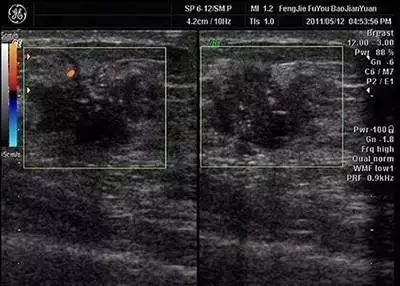

3.腺体结构紊乱

乳腺细胞数量、排列及组织结构

看起来与正常的不同

解读:在乳腺超声或钼靶报告里较为常见的一个形容腺体图像的描述性语言。如果乳腺影像结构看起来与正常的不同,我们就会形容为“腺体结构紊乱”,多数是由于腺体增生(微观上就是细胞数量、排列及组织结构的改变)所致,就是人们常说的“乳腺增生”,当然也不能排除极少数“结构紊乱”是因为局部细胞的恶变所致。